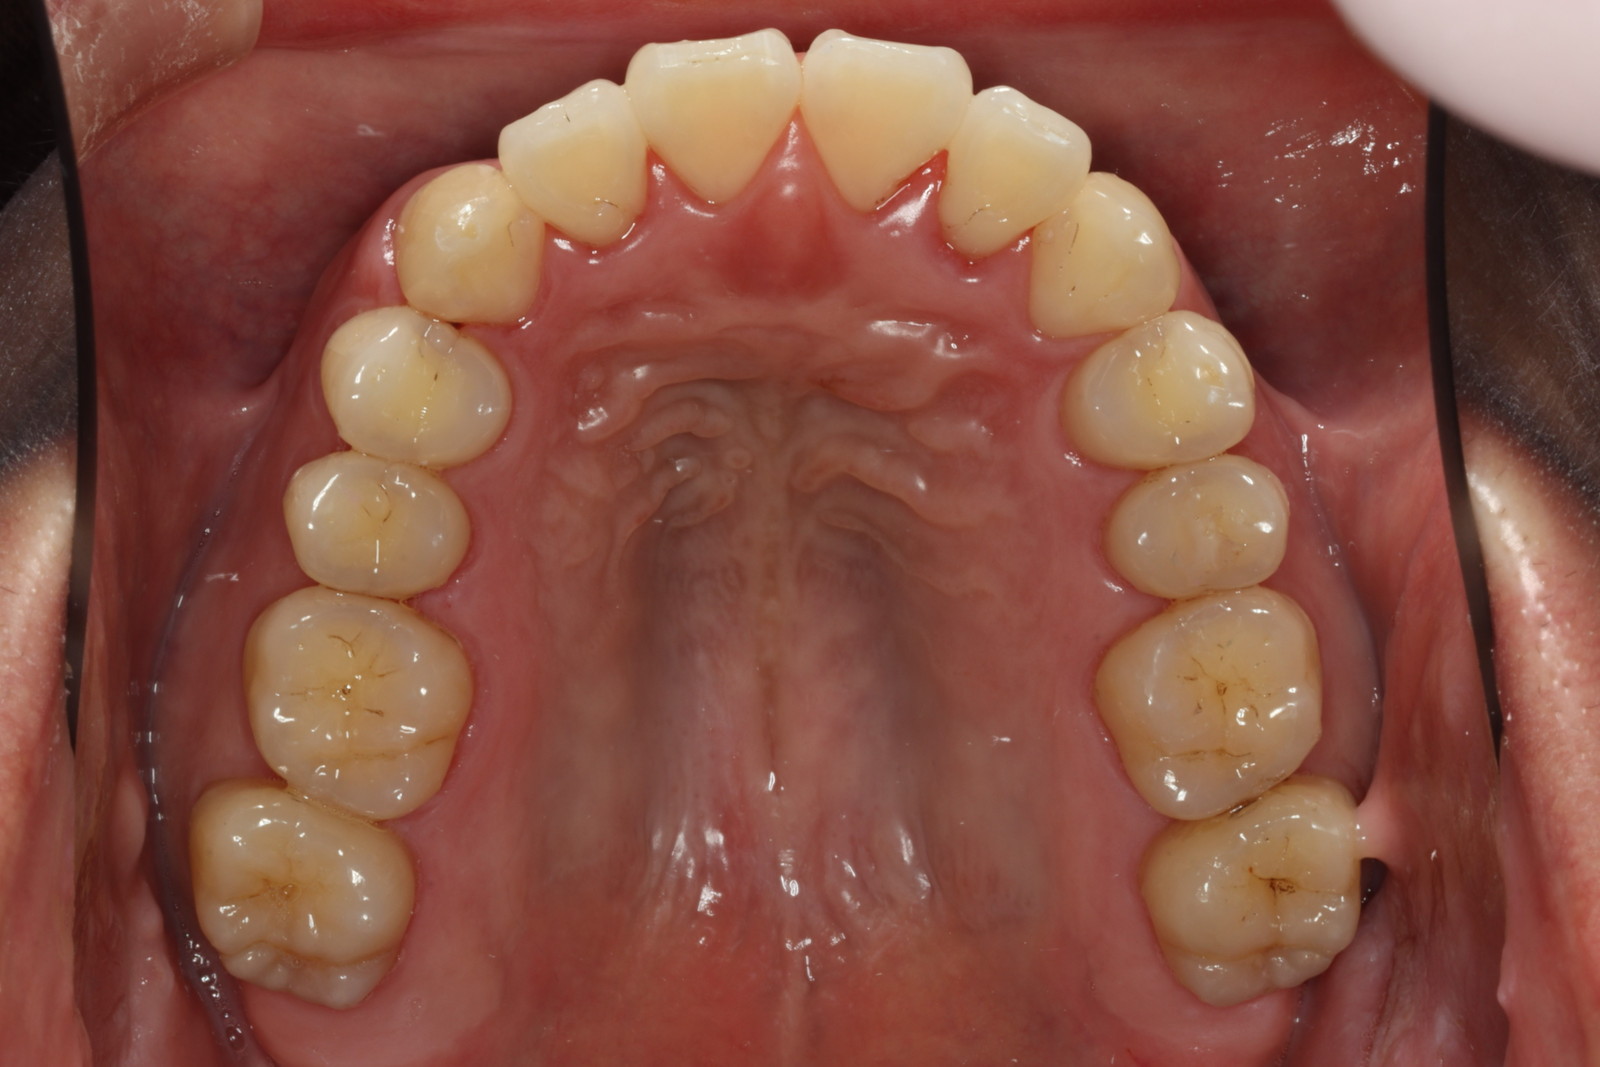

問診を行い、お口の悩みや希望を確認します。レントゲン撮影や口腔内写真の撮影など、必要に応じた精密検査を行います。